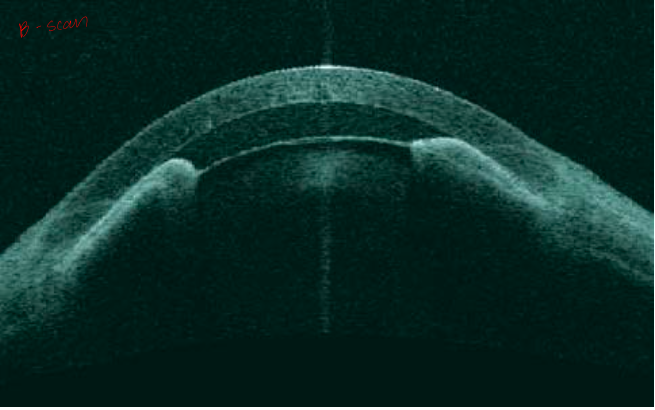

Case 8 anterior B-scan

normal curvature of the iris

angle closed the whole way (periphery and central)

no iris bombe